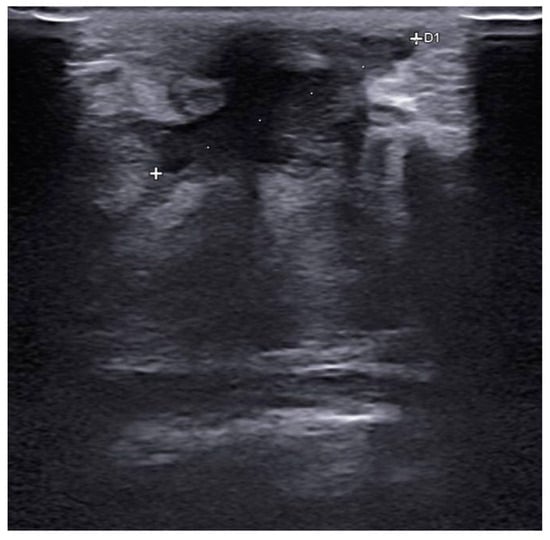

Before surgery, all patients underwent breast ultrasound to assess the presence of an abscess or fistula. Regarding clinical and radiological presentation, 12 patients presented with an abscess in the form of a painful and tender breast mass, with tense and reddened skin but no cutaneous fistula, confirmed by ultrasound (Figure 1, Figure 2 and Figure 3); two patients presented with an abscess associated with periareolar fistula (Figure 4), visible on breast ultrasound; five patients showed signs of a past abscess with negative preoperative ultrasound findings, and among them, one had a fistulous tract without purulent discharge (Table 1). The location of abscesses, fistulas, and their sequelae was the periareolar area in all patients. Additionally, four patients presented with bilateral symptoms. For patients with active abscesses at surgery, the mean size of the abscess cavity was 28.7 mm.

Figure 2. Abscess with a maximum extent of 25 mm, reaching close to the subcutaneous tissue.